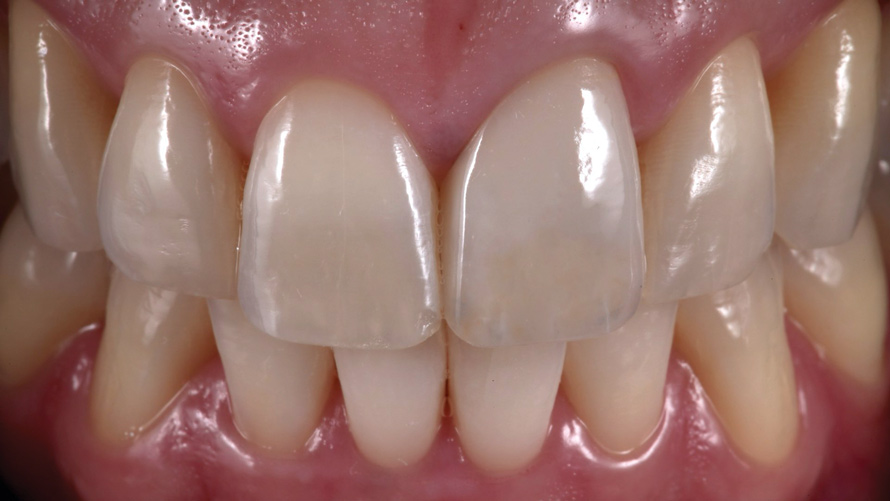

Eight weeks after the initial start of the walking bleach procedure, the final layered lithium disilicate crown was tried-in and evaluated for function and esthetics. Upon patient approval, the intaglio surface of the crown was etched for 20 seconds with a 9.6% hydrofluoric acid etchant, rinsed, and then scrubbed with a 37.5% orthophosphoric acid solution to clean out any ceramic debris. The crown was then placed into an ultrasonic bath of 91% isopropyl alcohol for 5 minutes, after which the intaglio surface was coated with silane and placed under a warm air dryer for 1 minute. A translucent self-adhesive resin cement was used to bond the final restoration to the preparation. The patients both stated that they approved of the form, function, and esthetics of the definitive restoration and that they were very pleased with the final results (Figure 13 through Figure 18). Routine periodic evaluations and radiographs were scheduled to monitor their oral health and esthetics.

(16.) Case 2: Retracted full-smile view of the definitive all-ceramic restoration on the maxillary left central incisor.

Figure 16